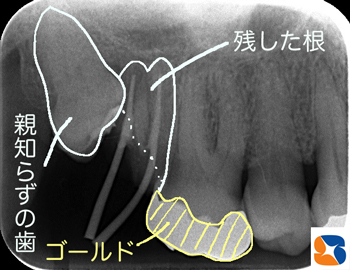

⑶〈結果のレントゲン〉

①残した根の上に

②補強した根(金属製)をジョイント。

さらにその上から

③ゴールド製の被せ物を装着。